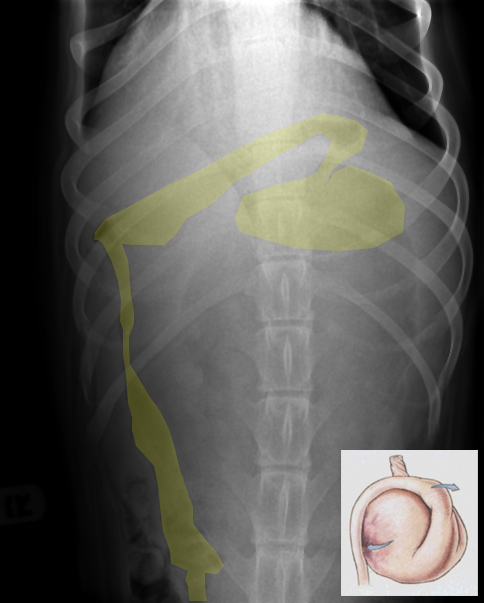

On note en premier lieu que l’estomac est fortement distendu par un mélange de gaz et de liquide (flèches jaunes) mais, curieusement, les replis gastriques se retrouvent plutôt déplacés ventralement (têtes de flèche blanches) alors que la partie dorsale de l’estomac, qui est soulignée par le gaz et devrait pourtant correspondre au fundus, est lisse. On note aussi la présence d’une dilatation importante de l’oesophage thoracique caudal (flèche blanche), trouvaille fréquemment associée au volvulus gastrique. Une structure irrégulière remplie de gaz est superposée à la partie craniodorsale de l’estomac (ovale bleu) alors que toutes les anses du petit intestin et le colon sont repoussés loin caudalement par l’estomac dilaté. Il persistait donc un doute à l’effet que cette structure pouvait être l’antre pylorique faiblement distendue. Enfin, la rate est repliée sur elle-même avec une forme de «C» inversé (en rouge), indiquant une position anormale de la tête avec soupçon de la présence d’une torsion splénique. Le détail des séreuses reste bon et je ne voyais pas de pneumatose de la paroi.

À la lumière de toutes ces trouvailles, je craignais fortement que nous étions en présence d’un volvulus gastrique d’apparence radiographique atypique avec torsion splénique concomitante. J’ai donc recommandé une projection orthogonale afin de valider cette hypothèse.

Sur la projection VD obtenue, la jonction gastroduodénale se retrouve dans le quadrant cranial gauche de l’abdomen, ce qui est une position anormale et confirme un volvulus gastrique. Il semble cependant incomplet, ce qui explique probablement l’absence de la compartimentation pathognomonique.